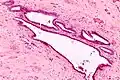

High magnification micrograph of endosalpingiosis, showing the characteristic cystic spaces lined by a simple epithelium with cilia. H&E stain. | |

It is characterized by cysts with tubal-type epithelium (e.g. ciliated epithelium) surrounded by a fibrous stroma. It is not often associated with hemorrhage.